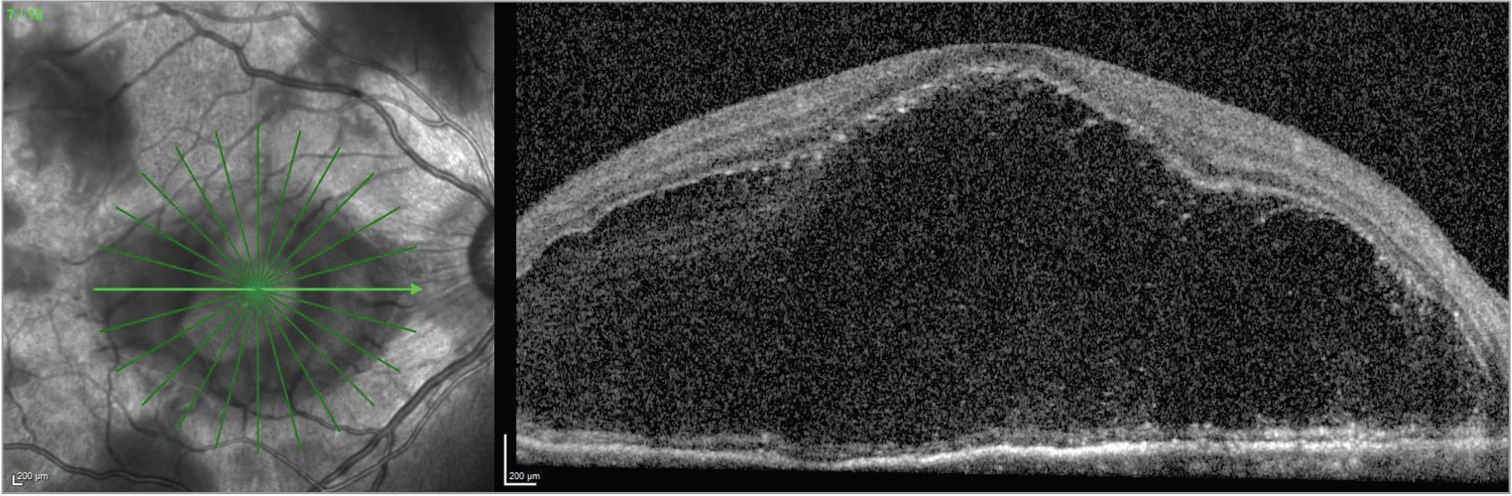

| Figure 5. OCT of the right eye demonstrating a massive bacillary detachment. |

In this case, the presence of a bacillary detachment was critical for making the diagnosis of VKH in a timely manner. “Bacillary” means “shaped like a rod”; a bacillary layer detachment is named as such because photoreceptors are approximately rod-shaped, and the detachment involves splitting of the photoreceptors at the level of the inner segment myoid. It can be recognized on OCT as fluid between the ellipsoid zone and the external limiting membrane.

In terms of mechanism, one hypothesis is that a bacillary layer detachment occurs when the accumulation of subretinal fibrin modulates the adhesion between the photoreceptor outer segments and the apical microvilli of the retinal pigment epithelium.6 Subretinal exudation then exerts hydrostatic pressure, leading to the bacillary layer detachment.